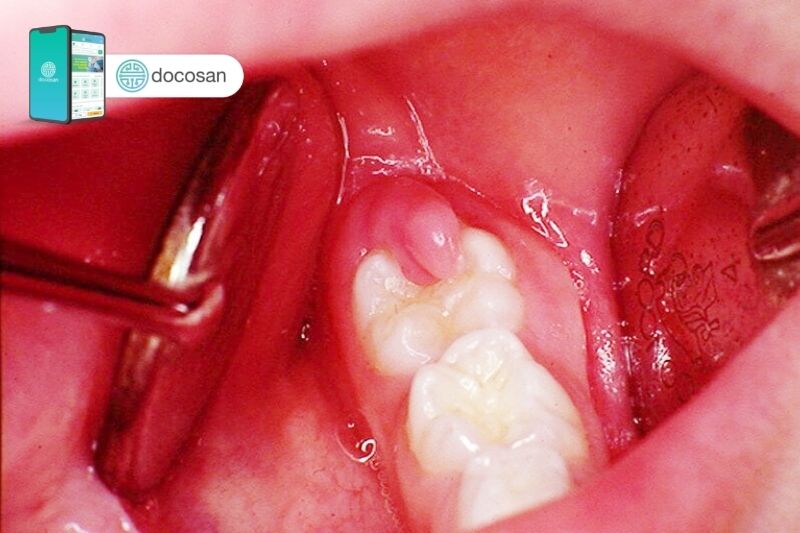

Bên cạnh đó, một số trường hợp viêm lợi trùm do răng không xé phần nướu bao phủ để chui ra, khi đó các mảng bám thức ăn và vi khuẩn có thể sinh sôi và phát triển trong đó dẫn đến tình trạng viêm nướu. Nếu không được điều trị có thể tạo nên các ổ áp xe, lâu ngày ảnh hưởng đến các mô nha chu bên cạnh, tệ hơn có thể gây mất răng. Sưng nướu răng khôn có thể biểu hiện các bệnh lý từ nhẹ đến nặng nên người bệnh không được xem nhẹ nếu như tình trạng sưng nướu cứ kéo dài.

- Trong trường hợp viêm lợi trùm, chỉ định rạch nướu răng giúp giải thoát răng khôn nằm bên dưới là cần thiết. Khi đó răng sẽ được bộc lộ ra bên ngoài, khoảng trống giữa răng và nướu trước đó sẽ được loại bỏ nhằm làm mất môi trường sinh sống của vi khuẩn giúp hạn chế sự sinh sôi và phát triển của chúng.